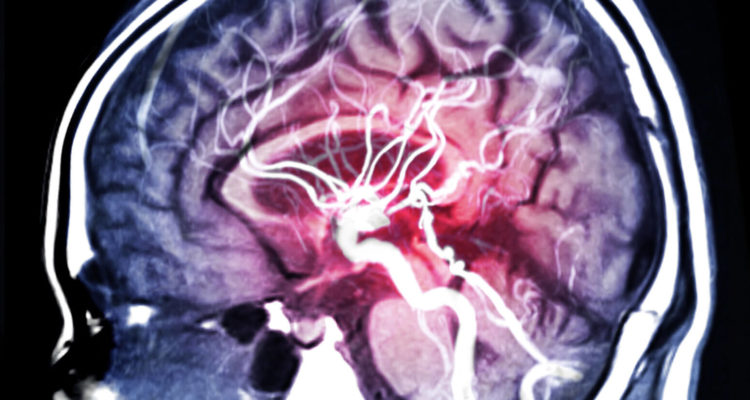

Лікарі знайшли спосіб знизити ризик інсульту та ішемічної хвороби

Серцево-судинні захворювання вважаються однією з найчастіших причин передчасної смерті в світі. За деякими оцінками, від них щорічно помирає близько